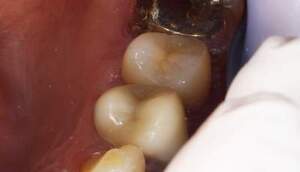

MTM開始直後と、終了後です。フックの位置が変わっているのがわかると思いますが、それが歯が動いた証拠となります。

MTM中。頬側には審美面の回復のために仮歯がついています。

歯からはフック、隣り合った歯にはワイヤーが渡してあります。そこにゴムをひっかけて歯を挺出させます。